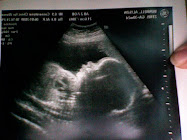

i have my next appointment this monday morning, and even though he is moving like usual now (A LOT) i still feel weird. why didn't i feel him for 2 days? was this a sign that something may be wrong? to ease my mind, i'm going to ask for an ultra sound on monday. i think seeing him will help me a lot!